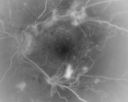

TRD-mosaic of OD

LUCY-MOSAIC-OD-TRD.jpg

1 files, last one added on May 22, 2012

Album viewed 654 times